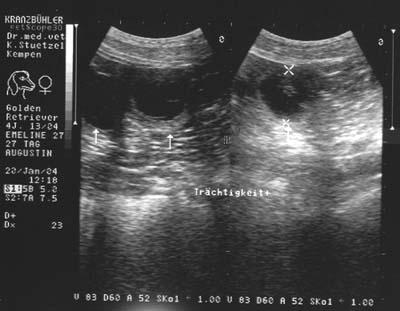

Emmi war trächtig.

Wieder warten und es sollte ein kleiner Wurf werden.

Emmi mit 54 Tagen der Trächtigkeit.

Sie hatte kaum Bauch.

Es war nun auch für mich klar, dass es ein sehr kleiner Wurf werden würde

Emmi mit 56 Tagen